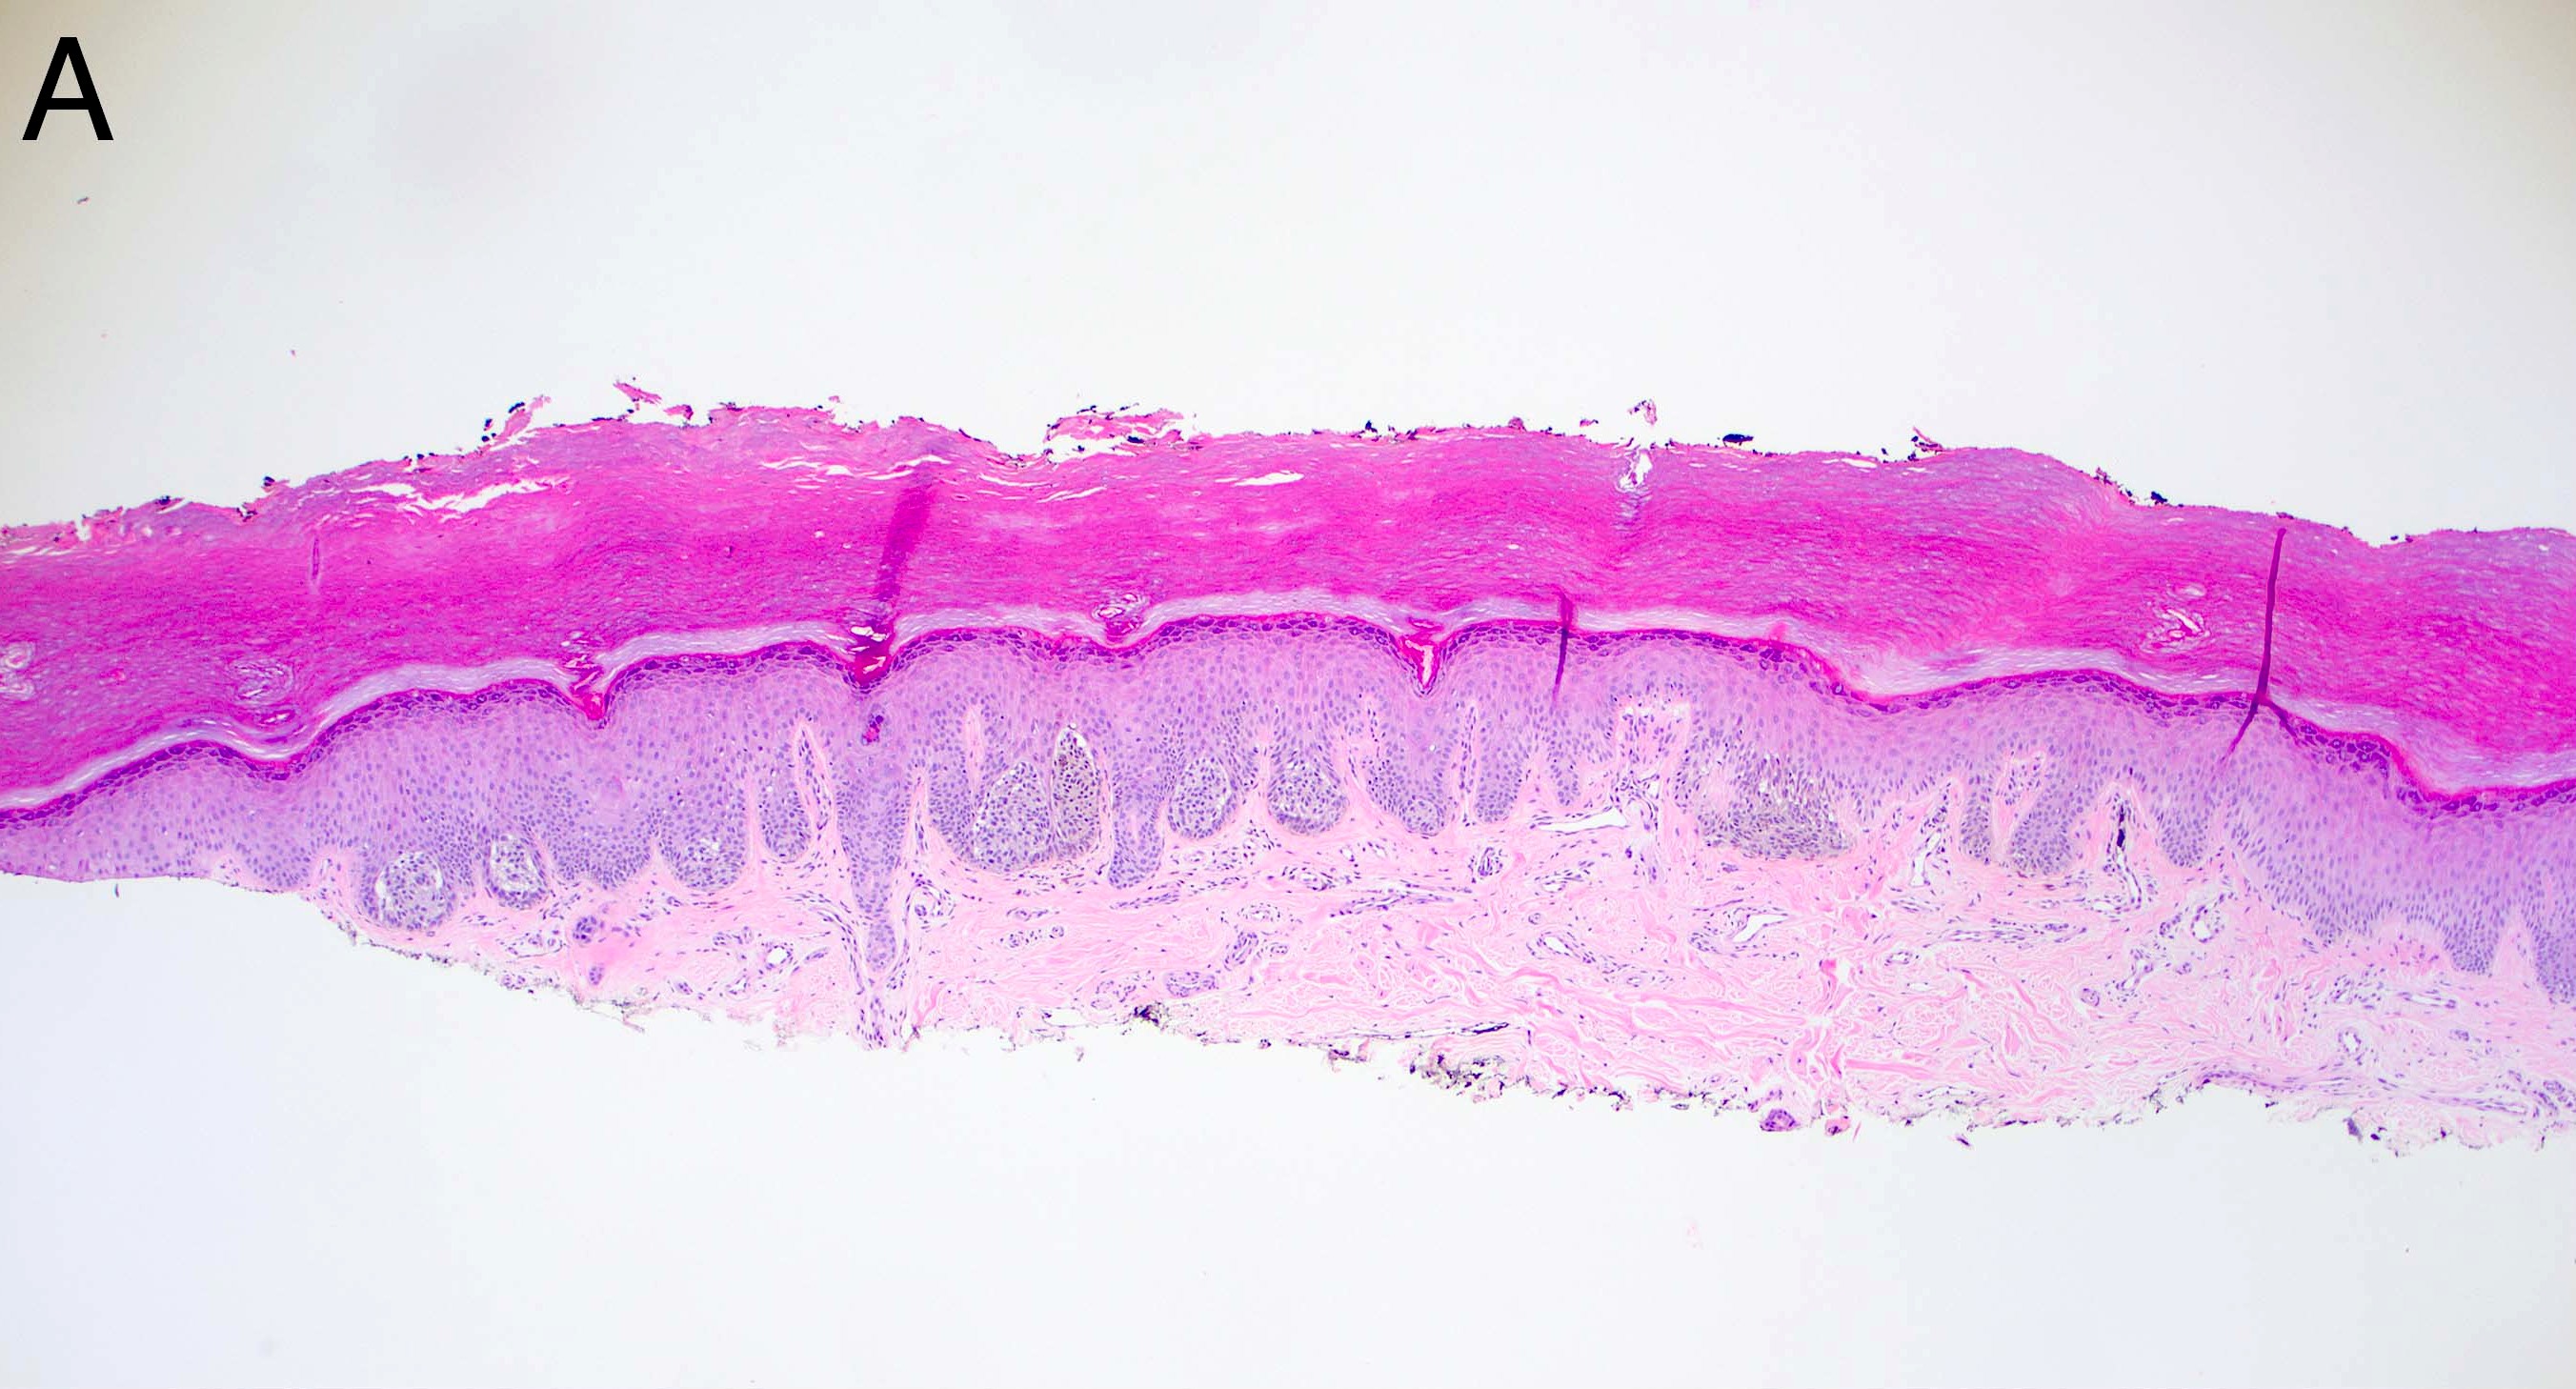

Microscopic (histologic) images

- Melanocytic nevi of the scalp (Am J Dermatopathol 2016;38:867):

- Melanocytes can be enlarged with irregular nuclei but atypia should be uniform throughout the nevus

- May contain large irregular nests in close proximity to one another

- Lentiginous growth may be prominent

- Pagetoid spread is a common feature

- Lesion can have broad junctional involvement and involve adnexa

- Single cell dispersion can be seen at lateral edges

- Lateral circumscription and maturation should be maintained, however symmetry may be lost (Am J Dermatopathol 2016;38:867)

- Prominent stromal fibrotic response can be seen